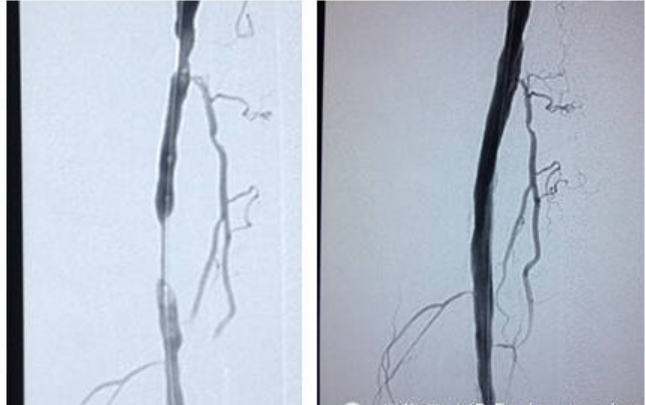

2014年12月20日,Reewarm®外周球囊扩张导管的首例临床病例植入北京市中日友好医院顺利完成。

此次首例患者手术病灶长度非常长,应用 Reewarm 外周球囊扩张导管充分扩张,术后造影显示血管非常通畅,手术成功